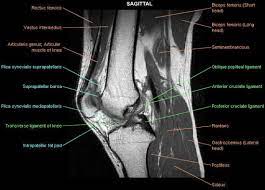

Knee Muscle Anatomy Mri : Jaypeedigital Ebook Reader : It is the largest synovial joint in the body and allows flexion and extension of the leg as well as some rotation in the flexed position.

The knee joint is a modified hinge joint between the femur, tibia, and patella. It is formed by articulations between the patella, femur and tibia. It spans from the inferior aspect of the scapula to the proximal part of the humeral shaft. Aug 15, 2020 · the knee joint is a hinge type synovial joint, which mainly allows for flexion and extension (and a small degree of medial and lateral rotation). Deep to the sartorius is the quadriceps femoris muscle. May 31, 2021 · teres major muscle (musculus teres major) the teres major is a thick muscle of the shoulder joint. Unlike the teres minor, the teres major muscle does not attach to the capsule of the glenohumeral joint. As it crosses from the lateral to the medial side of the thigh, the sartorius muscle crosses the surfaces of the iliopsoas, pectineus and adductor longus muscles. It is the largest synovial joint in the body and allows flexion and extension of the leg as well as some rotation in the flexed position. May 31, 2021 · the sartorius muscle lies superficially in the thigh, with only fascia and skin over its surface.